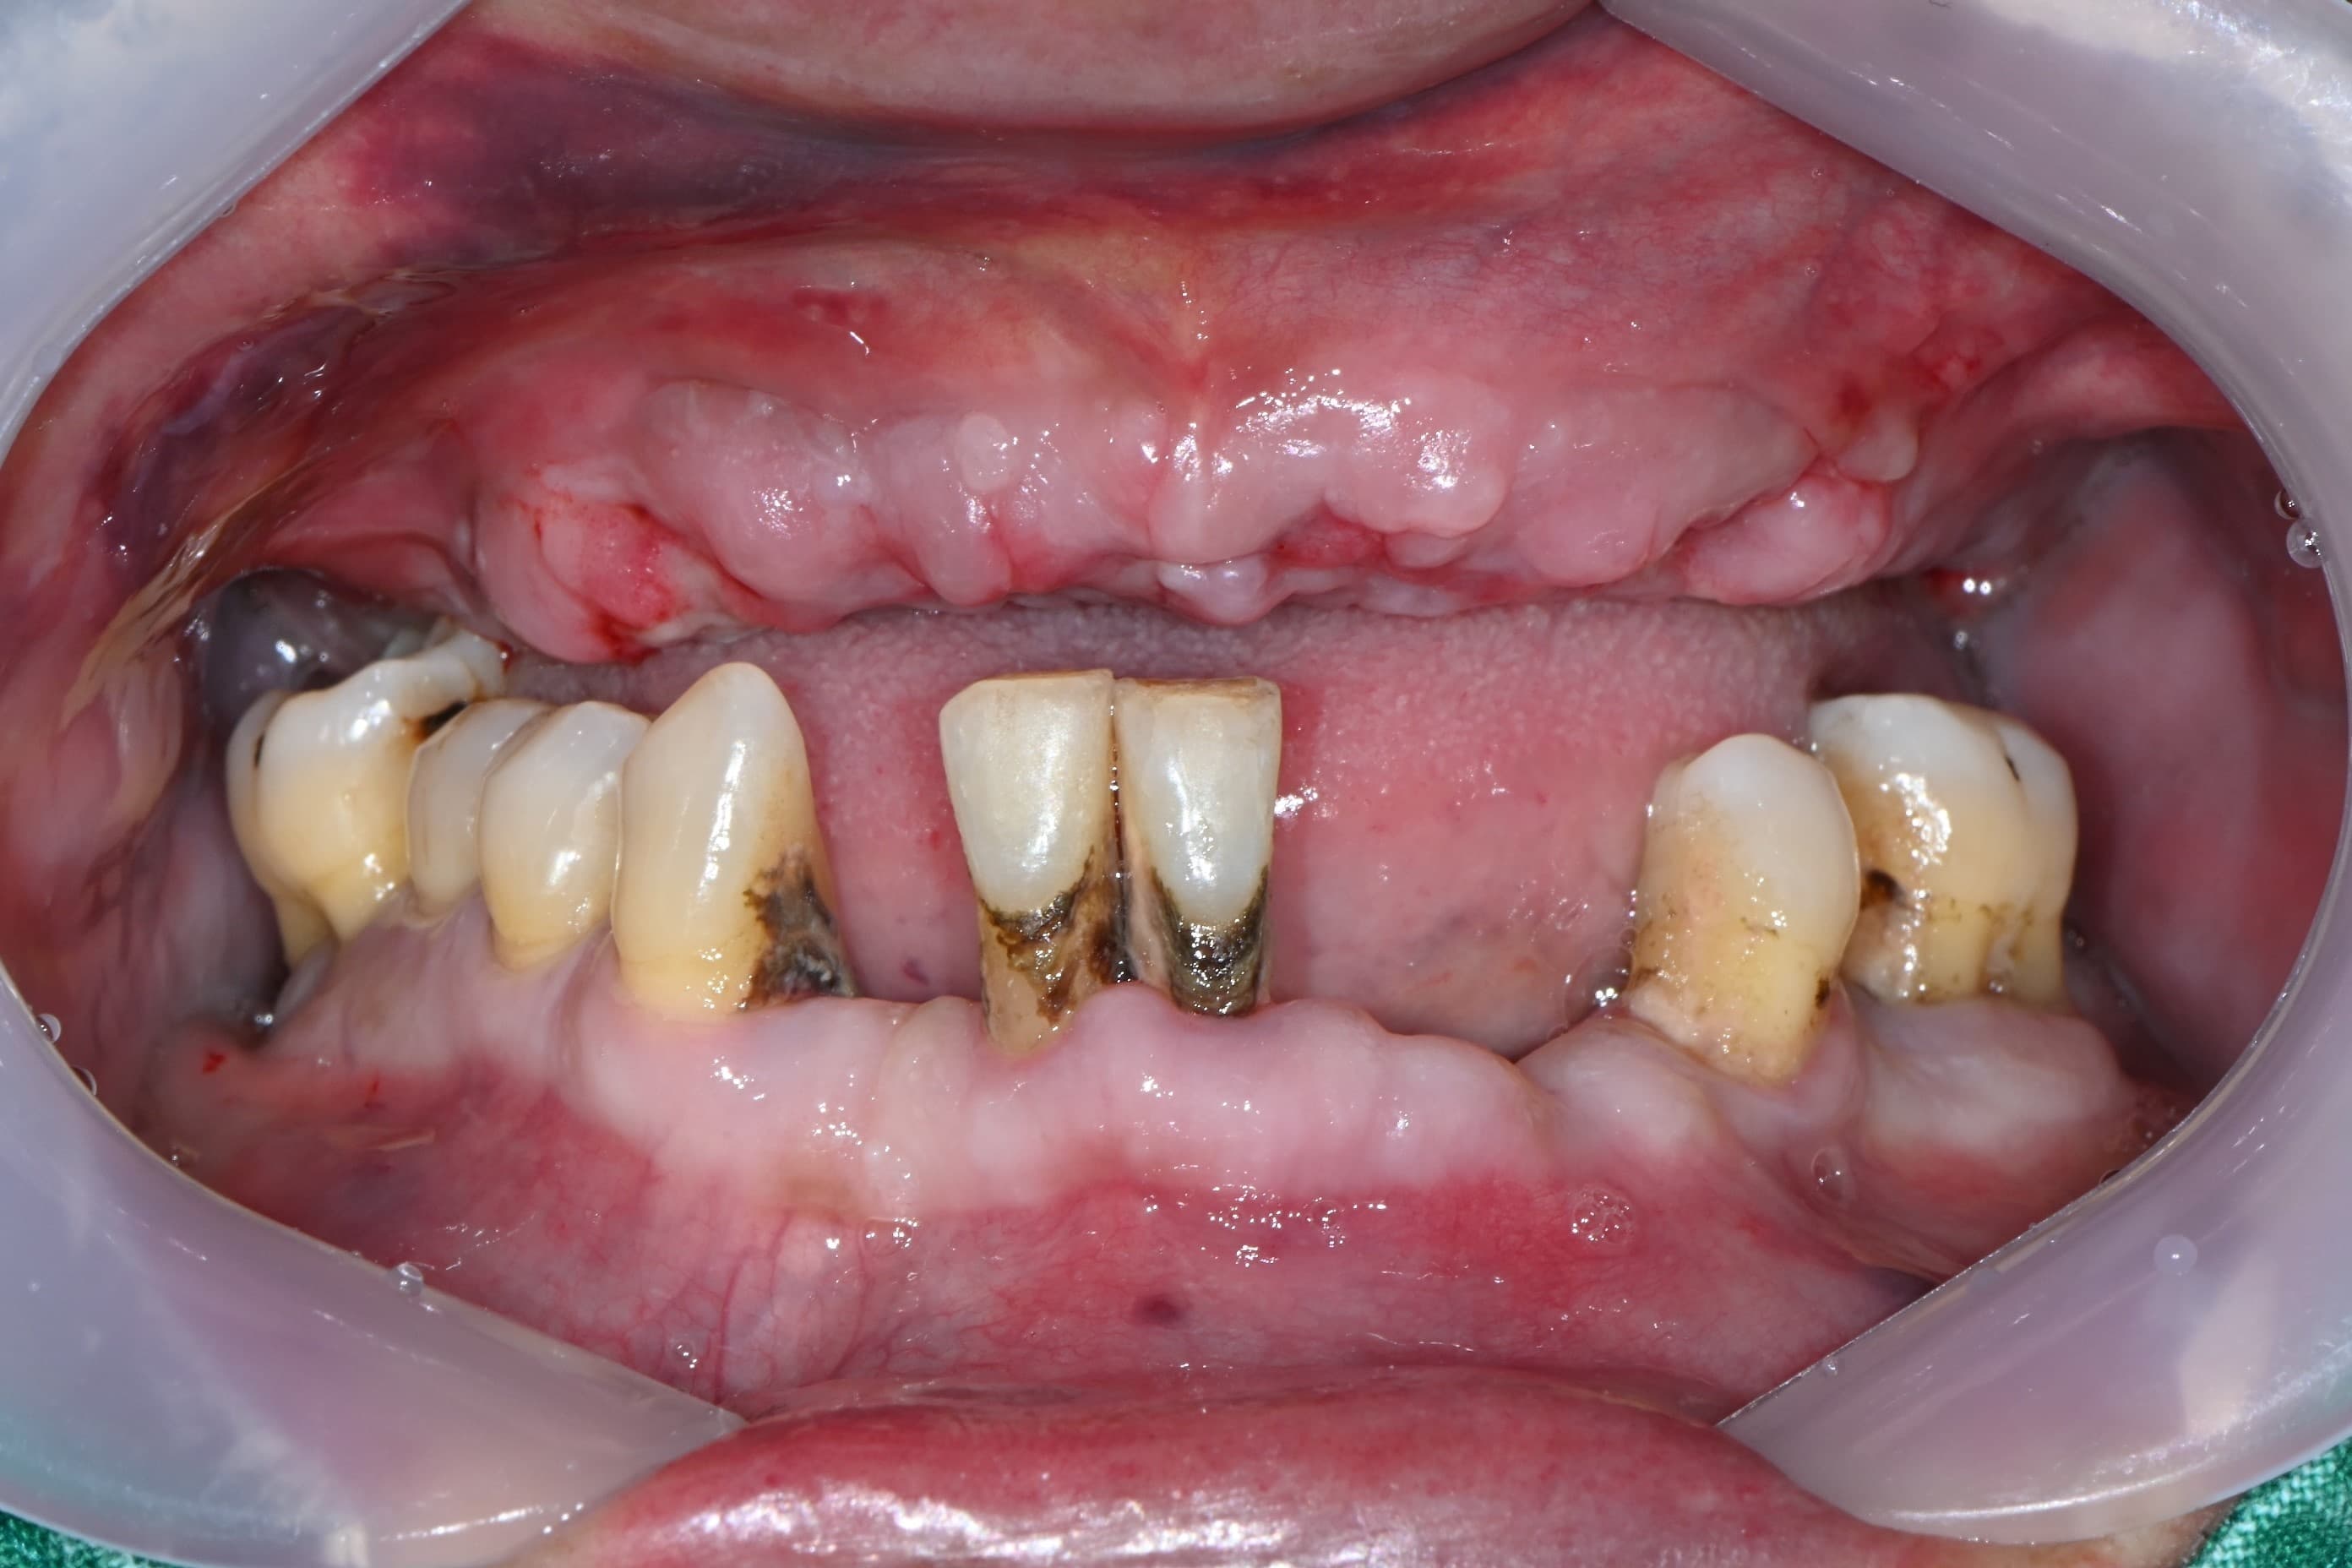

박●● · 남성

전악 임플란트 · 실제사진

WHY GODUK FIRST